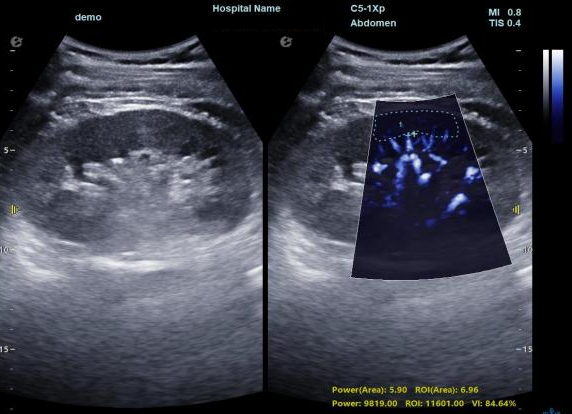

3) 通过血管指数(VI)定量评估局部血管密度,以定量化数据实时监测血流灌注情况,预判肾功能恢复情况;

微米级超高分辨率血流信号显像

肾脏的灌注评估,RI/VI量化数据

超微视血流显像评估肾移植术后灌注情况

这一项无创、无辐射操作简便且无需造影剂的黑科技,相当于用"高速摄像机"记录血液细胞的运动轨迹,让血管并发症"无处遁形。